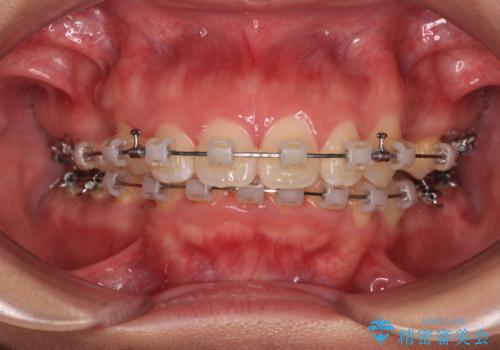

- 矯正装置

- クリアブラケット

- 2年7ヶ月